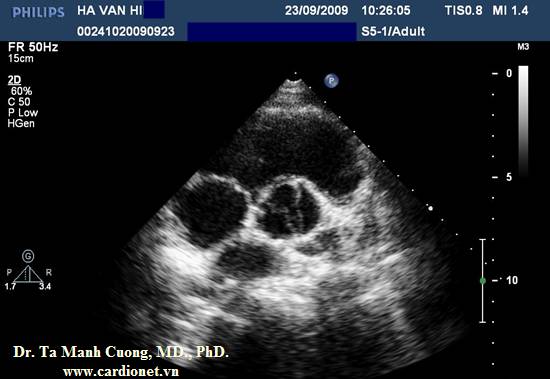

Một bệnh nhân khác: Hở chủ nhẹ, động mạch chủ chỉ có hai lá van:

- Trong thì tâm thu: